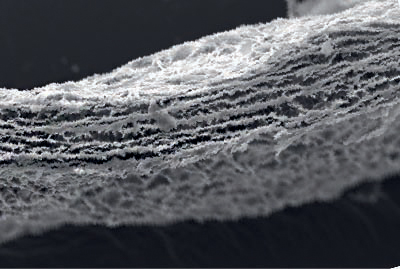

PURIFICACION

Membrana biocompatible gracias a una innovadora tecnología de procesamiento.

El proceso de limpieza patentado con dióxido de carbono supercrítico (scCO2) elimina suavemente los componentes no deseados (por ejemplo, células, lípidos) mientras que la matriz de colágeno natural y el entrelazado natural de las fibras de colágeno son preservados.